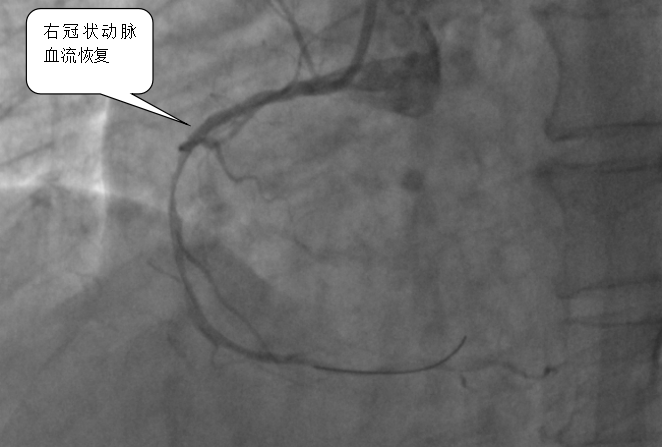

医院心血管内科专家团队立即启动胸痛中心绿色通道,从患者入院到完成心电图检查仅用3分钟,确诊后2分钟内即给予抗血小板治疗,并紧急实施冠脉介入手术。术中造影发现患者右冠状动脉近段完全闭塞,医生通过血栓抽吸、冠脉内溶栓及药物球囊扩张等操作,最终成功植入支架,恢复血流。术后患者血压、心率恢复正常,转危为安。